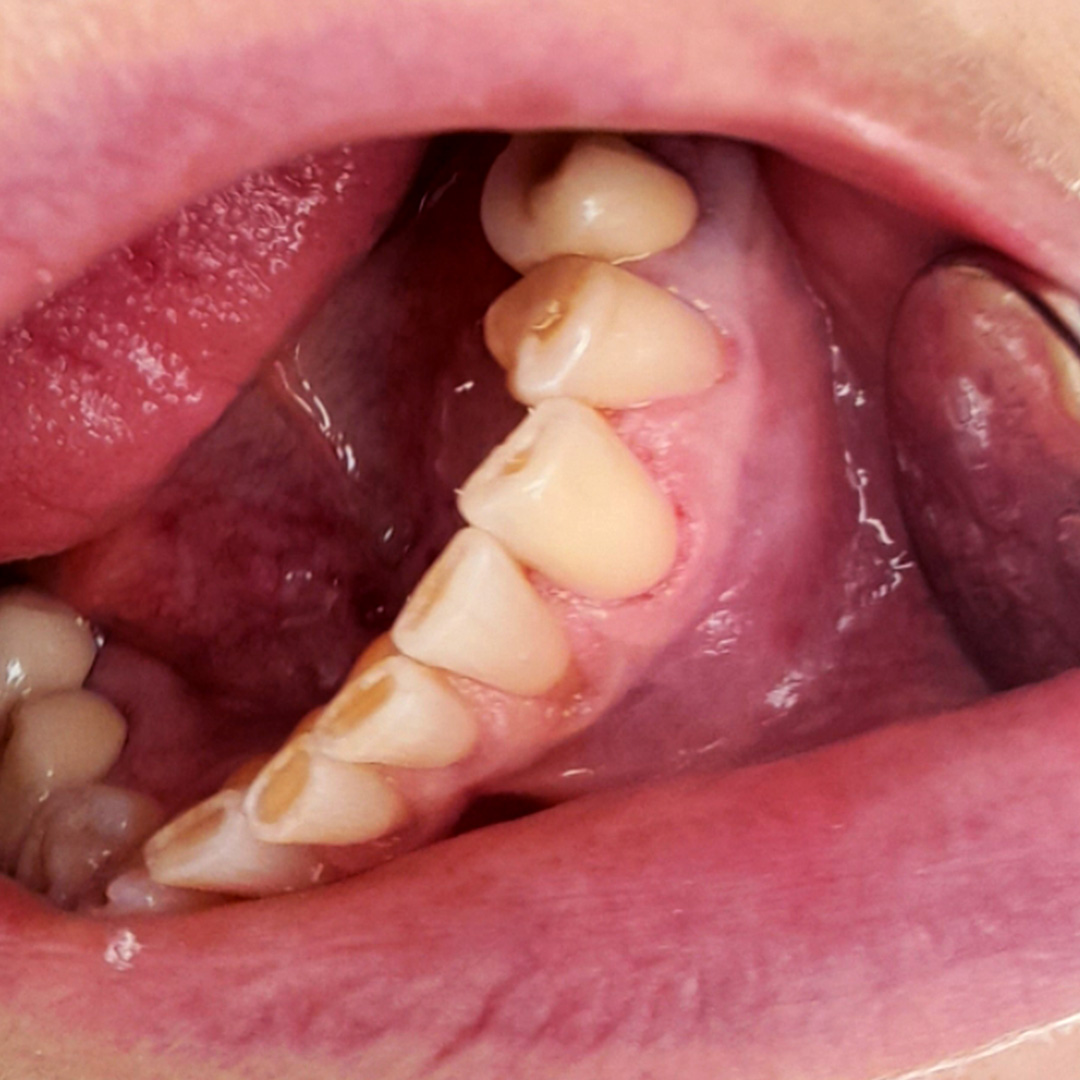

До и после лечения

В стоматологию обратилась пациентка с жалобами на быстро проходящую боль от холодного в районе клыка нижней челюсти. Врач провёл осмотр, а также реакцию зуба на холодный воздух и зондирование. В результате выявлена кариозная полость. Поставлен диагноз — средний кариес зуба 3.3 (вестибулярно). Проведено лечение с использованием композита светового отверждения Эстелайт.

В ходе лечения врач провёл следующие манипуляции:

- инфильтрационная анестезия;

- ретракция десны нитью;

- механическая и медикаментозная обработка кариозной полости;

- наложение изолирующей прокладки;

- постановка пломбы из материала Эстелайт.